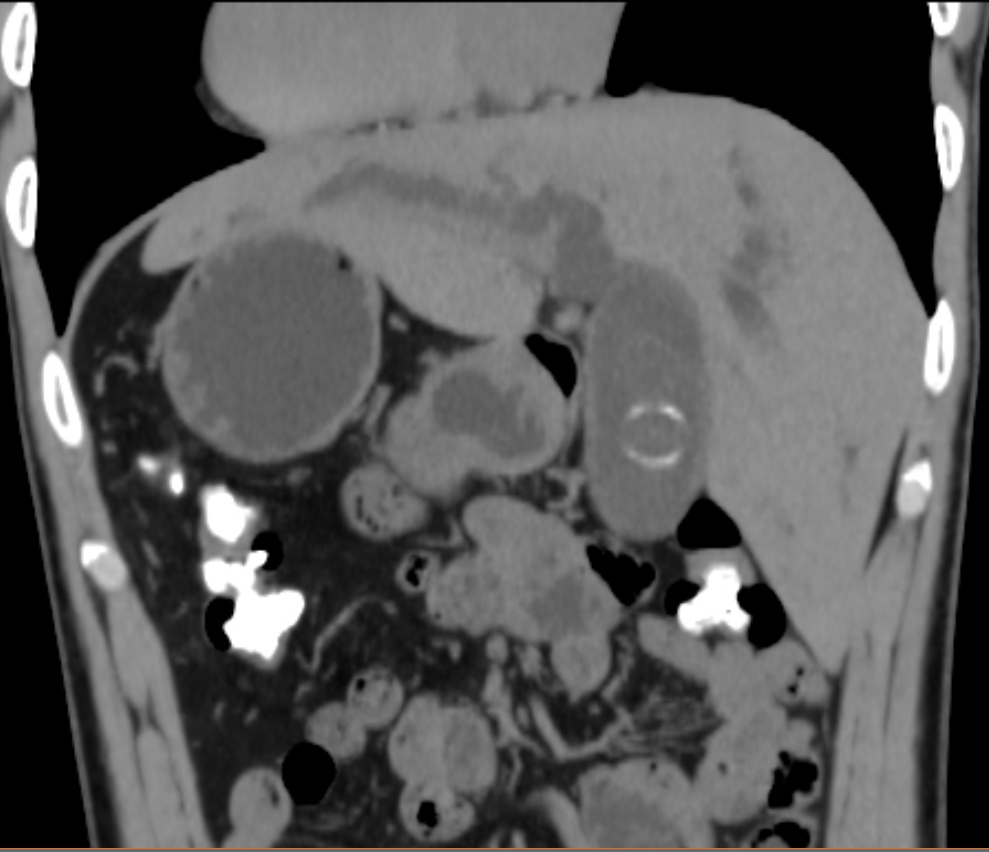

反转的脏器CT影像

患者陈先生因腹痛、肤黄就诊当地医院,经检查确诊为胆总管结石伴胆管炎。然而影像检查提示:右位心,完全内脏反位。面对这百万分之一的变异,当地的医生束手无策。陈先生慕名来到孟超肝胆医院就诊。